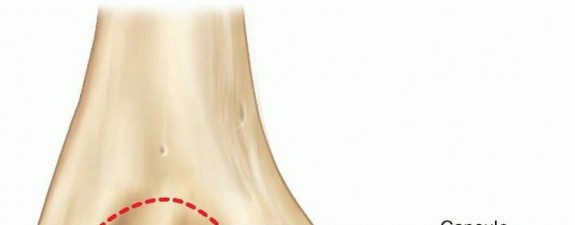

Chapter 35 Pediatric Ankle Fractures Scott J. Mubarak Andrew T. Pennock DEFINITION Ankle fractures account fo…